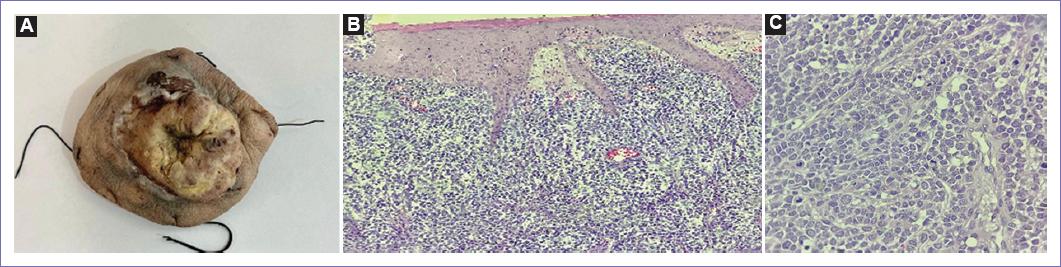

Se envía al servicio de patología un tumor de 12 × 11 × 4 cm fungiforme, ulcerado, así como múltiples ganglios en región inguinal de 1.5 cm y el mayor de 5 cm.

En el informe de patología se reporta CCM, de 12.5 × 10 × 3 cm con piel rugosa, ulcerada y ahulada que contiene lesión central nodular indurada y umbilicada que mide 8 × 7 × 2.5 cm, con tasa mitótica de 61 mitosis por mm2, con márgenes negativos a neoplasia. En pieza enviada como linfadenectomía pélvica se disecaron 23 ganglios, los cuales fueron positivos para malignidad (Fig. 3).

Figura 3 A: huso de piel de 12.5 × 10 × 3 cm con piel rugosa, ulcerada y ahulada que contiene lesión central nodular indurada y umbilicada que mide 8 × 7 × 2.5 cm. B y C: corte histológico donde se aprecia lesión difusa de bordes mal delimitados en dermis papilar y reticular. A mayor aumento conformado por células pequeñas, redondas y azules de aspecto epitelioide con nucleolos incospicuos con mitosis dispersas.